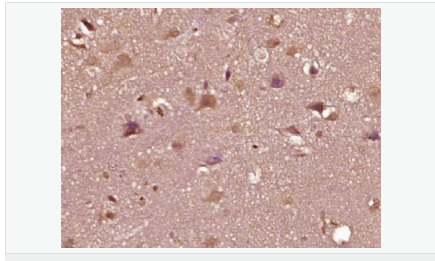

| 產(chǎn)品應(yīng)用 | WB=1:500-2000 ELISA=1:5000-10000 IHC-P=1:100-500 IHC-F=1:100-500 Flow-Cyt=1ug/Test IF=1:100-500 (石蠟切片需做抗原修復(fù)) not yet tested in other applications. optimal dilutions/concentrations should be determined by the end user. |

| 細(xì)胞定位 | 細(xì)胞核 細(xì)胞漿 |

| 產(chǎn)品介紹 | The androgen receptor gene is more than 90 kb long and codes for a protein that has 3 major functional domains: the N-terminal domain, DNA-binding domain, and androgen-binding domain. The protein functions as a steroid-hormone activated transcription factor. Upon binding the hormone ligand, the receptor dissociates from accessory proteins, translocates into the nucleus, dimerizes, and then stimulates transcription of androgen responsive genes. This gene contains 2 polymorphic trinucleotide repeat segments that encode polyglutamine and polyglycine tracts in the N-terminal transactivation domain of its protein. Expansion of the polyglutamine tract causes spinal bulbar muscular atrophy (Kennedy disease). Mutations in this gene are also associated with complete androgen insensitivity (CAIS). Two alternatively spliced variants encoding distinct isoforms have been described. [provided by RefSeq, Jul 2008] Function: Steroid hormone receptors are ligand-activated transcription factors that regulate eukaryotic gene expression and affect cellular proliferation and differentiation in target tissues. Transcription factor activity is modulated by bound coactivator and corepressor proteins. Transcription activation is down-regulated by NR0B2. Activated, but not phosphorylated, by HIPK3 and ZIPK/DAPK3. [ENZYME REGULATION] AIM-100 (4-amino-5,6-biaryl-furo[2,3-d]pyrimidine) suppresses TNK2-mediated phosphorylation at Tyr-267. Inhibits the binding of the Tyr-267 phosphorylated form to androgen-responsive enhancers (AREs) and its transcriptional activity. Subunit: Binds DNA as a homodimer. Part of a ternary complex containing AR, EFCAB6/DJBP and PARK7. Interacts with HIPK3 and NR0B2 in the presence of androgen. The ligand binding domain interacts with KAT7/HBO1 in the presence of dihydrotestosterone. Interacts with EFCAB6/DJBP, PELP1, PQBP1, RANBP9, RBAK, SPDEF, SRA1, TGFB1I1, ZNF318 and RREB1. Interacts with ZMIZ1/ZIMP10 and ZMIZ2/ZMIP7 which both enhance its transactivation activity. Interacts with SLC30A9 and RAD54L2/ARIP4. Interacts via the ligand-binding domain with LXXLL and FXXLF motifs from NCOA1, NCOA2, NCOA3, NCOA4 and MAGEA11. The AR N-terminal poly-Gln region binds Ran resulting in enhancement of AR-mediated transactivation. Ran-binding decreases as the poly-Gln length increases. Interacts with HIP1 (via coiled coil domain). Interacts (via ligand-binding domain) with TRIM68. Interacts with TNK2. Interacts with USP26. Interacts with RNF6. Interacts (regulated by RNF6 probably through polyubiquitination) with RNF14; regulates AR transcriptional activity. Interacts with PRMT2 and TRIM24. Interacts with GNB2L1/RACK1. Interacts with RANBP10; this interaction enhances dihydrotestosterone-induced AR transcriptional activity. Interacts with PRPF6 in a hormone-independent way; this interaction enhances dihydrotestosterone-induced AR transcriptional activity. Interacts with STK4/MST1. Interacts with ZIPK/DAPK3. Interacts with LPXN. Interacts with MAK. Part of a complex containing AR, MAK and NCOA3. Subcellular Location: Nucleus. Cytoplasm. Note=Predominantly cytoplasmic in unligated form but translocates to the nucleus upon ligand-binding. Can also translocate to the nucleus in unligated form in the presence of GNB2L1. Tissue Specificity: Isoform 2 is mainly expressed in heart and skeletal muscle. Post-translational modifications: Sumoylated on Lys-386 (major) and Lys-520. Ubiquitinated. Deubiquitinated by USP26. 'Lys-6' and 'Lys-27'-linked polyubiquitination by RNF6 modulates AR transcriptional activity and specificity. Phosphorylated in prostate cancer cells in response to several growth factors including EGF. Phosphorylation is induced by c-Src kinase (CSK). Tyr-534 is one of the major phosphorylation sites and an increase in phosphorylation and Src kinase activity is associated with prostate cancer progression. Phosphorylation by TNK2 enhances the DNA-binding and transcriptional activity and may be responsible for androgen-independent progression of prostate cancer. Phosphorylation at Ser-81 by CDK9 regulates AR promoter selectivity and cell growth. Phosphorylation by PAK6 leads to AR-mediated transcription inhibition. Palmitoylated by ZDHHC7 and ZDHHC21. Palmitoylation is required for plasma membrane targeting and for rapid intracellular signaling via ERK and AKT kinases and cAMP generation. DISEASE: Defects in AR are the cause of androgen insensitivity syndrome (AIS) [MIM:300068]; previously known as testicular feminization syndrome (TFM). AIS is an X-linked recessive form of pseudohermaphroditism due end-organ resistance to androgen. Affected males have female external genitalia, female breast development, blind vagina, absent uterus and female adnexa, and abdominal or inguinal testes, despite a normal 46,XY karyotype. Defects in AR are the cause of spinal and bulbar muscular atrophy X-linked type 1 (SMAX1) [MIM:313200]; also known as Kennedy disease. SMAX1 is an X-linked recessive form of spinal muscular atrophy. Spinal muscular atrophy refers to a group of neuromuscular disorders characterized by degeneration of the anterior horn cells of the spinal cord, leading to symmetrical muscle weakness and atrophy. SMAX1 occurs only in men. Age at onset is usually in the third to fifth decade of life, but earlier involvement has been reported. It is characterized by slowly progressive limb and bulbar muscle weakness with fasciculations, muscle atrophy, and gynecomastia. The disorder is clinically similar to classic forms of autosomal spinal muscular atrophy. Note=Caused by trinucleotide CAG repeat expansion. In SMAX1 patients the number of Gln ranges from 38 to 62. Longer expansions result in earlier onset and more severe clinical manifestations of the disease. Note=Defects in AR may play a role in metastatic prostate cancer. The mutated receptor stimulates prostate growth and metastases development despite of androgen ablation. This treatment can reduce primary and metastatic lesions probably by inducing apoptosis of tumor cells when they express the wild-type receptor. Defects in AR are the cause of androgen insensitivity syndrome partial (PAIS) [MIM:312300]; also known as Reifenstein syndrome. PAIS is characterized by hypospadias, hypogonadism, gynecomastia, genital ambiguity, normal XY karyotype, and a pedigree pattern consistent with X-linked recessive inheritance. Some patients present azoospermia or severe oligospermia without other clinical manifestations. Similarity: Belongs to the nuclear hormone receptor family. NR3 subfamily. Contains 1 nuclear receptor DNA-binding domain. SWISS: P10275 Gene ID: 367 Database links: Entrez Gene: 367 Human Entrez Gene: 11835 Mouse Omim: 313700 Human SwissProt: P10275 Human SwissProt: P19091 Mouse Unigene: 496240 Human Unigene: 39005 Mouse Unigene: 394224 Mouse Unigene: 439657 Mouse Unigene: 9813 Rat Important Note: This product as supplied is intended for research use only, not for use in human, therapeutic or diagnostic applications. AR是一個(gè)由917個(gè)氨基酸組成的蛋白質(zhì),位于雄激素靶組織細(xì)胞中或細(xì)胞表面上的特異分子部位或結(jié)構(gòu)。 AR在前列腺癌中起著重要的作用,研究表明AR的表達(dá)與組織分型形成一定的相關(guān)性 ,AR在高分化的腫瘤中表達(dá)較多,而在低分化的腫瘤中表達(dá)較少。用于前列腺癌的檢測,指導(dǎo)臨床治療,目前可用于乳腺癌、食道癌等各項(xiàng)腫瘤的研究。 |